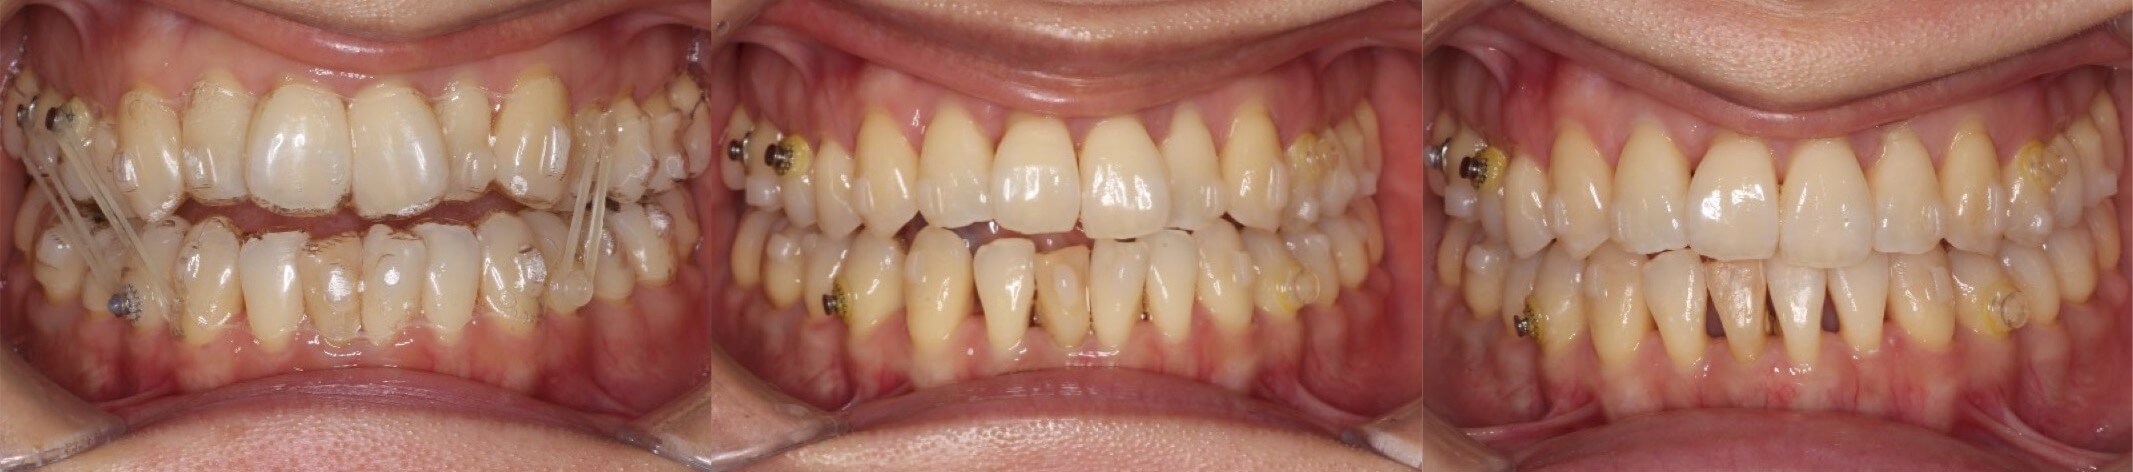

53歳女性・マウスピース型矯正装置

上顎歯列の後方移動を行う際、ふつうは親知らずの抜歯が必要になります。ですが、ミドルエイジの矯正治療では、できるだけ歯数を減らさないように計画を立てます。本治療では、歯科矯正用アンカースクリューを併用することで、達成いたしました。

<症例概要>

主訴:前のねじれと突出

年齢・性別:53歳女性

住まい:千葉県八千代市

症状:下顎後退・上下顎前歯唇側傾斜・叢生・左上7番欠損

治療方針:上顎歯列遠心移動

治療装置:マウスピース型矯正装置(アライナー装置)

固定装置:歯科矯正用アンカースクリュー・II級ゴム

治療期間:1年5か月

アライナー枚数:43+23(7日交換)

リテーナー:上下フィックスタイプ+クリアタイプ

治療費用:990,000(税込)

代表的副作用:痛み・治療後の後戻り・歯根吸収・歯髄壊死・歯肉退縮

▶︎その他の副作用

【治療シミュレーション】

II級ゴムとアンカースクリューからの顎内ゴムで上顎歯列を後方移動させています。

※マウスピース型カスタムメイド矯正歯科装置は完成物薬機法対象外の矯正装置であり、医薬品副作用被害救済制度の対象とはならない可能性があります。